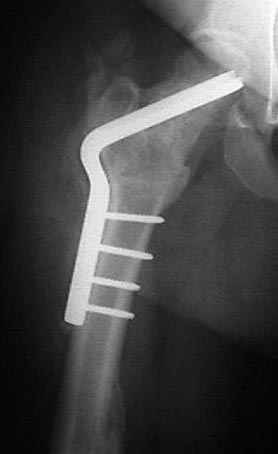

Несколько снимков из моей коллекции, чтобы разьяснить, почему мы до сих пор делаем различные варианты остеотомии.

N3 рисунок окончательный снимок, после операции моя рентгенограмма должен выглядеть примерно как эта картина. На N4 снимке клин перед удалением; N5 послеоперации 3 нед.; N6 окончательная рентгенограмма.

варус при проксимальном отделе 95 градусной пластиной.